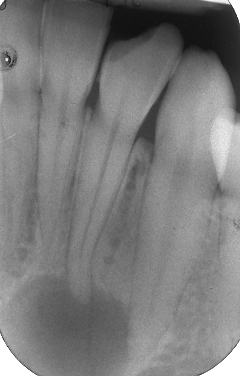

L'esecuzione di una corretta terapia canalare con il rispetto di tutte le sue fasi: preparazione e sagomatura, irrigazione canalare dinamica e una otturazione tridimensionale ed ermetica ha permesso la risoluzione del caso di grossa lesione periapicale di diametro superiore ad 1,2cm a carico dell'incisivo laterale senza effettuare nessun trattamento chirurgico proposto al povero paziente. L'indagine radiologica usata in sequenza nel tempo permette di verificare l''involuzione dello stato infiammatorio dopo la terapia canalare.